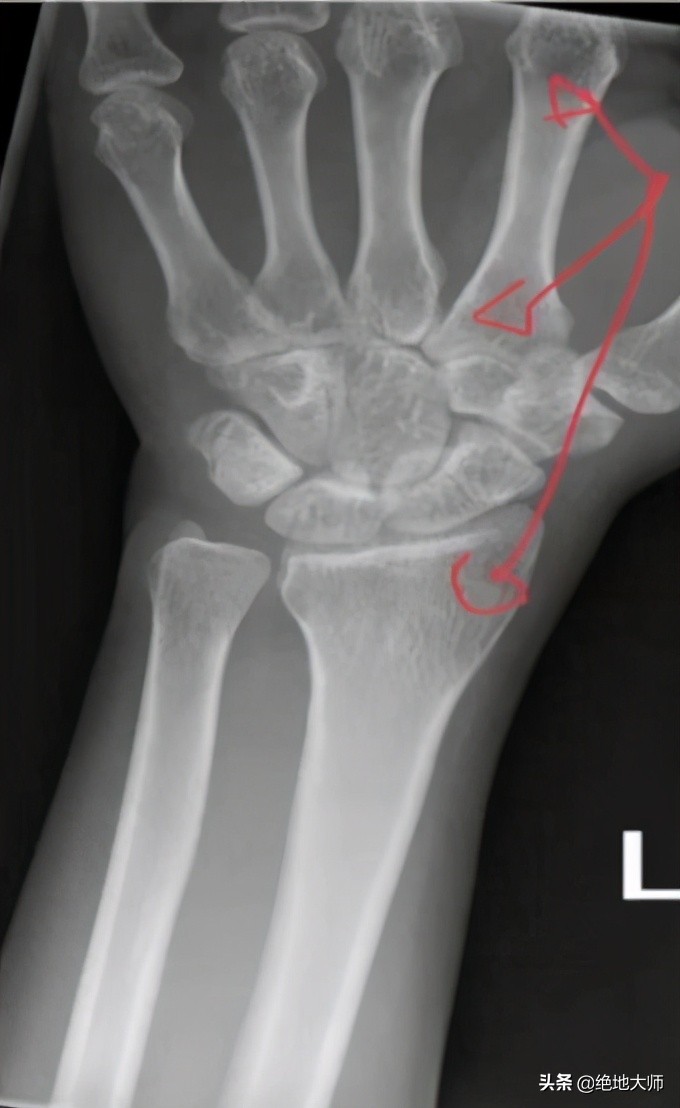

Case study: upper extremity crush injury

The patient was getting out of a Taxi when the car door was slammed onto the dorsal side of his left hand. 患者正从出租车里出来时,车门被砰地撞在他的左手背侧上。

There was no fracture but about one month later he began to get terrible pain along his entire arm from hand to shoulder. 没有骨折,但大约一个月后,他开始整个手臂从手到肩部都疼痛难忍。